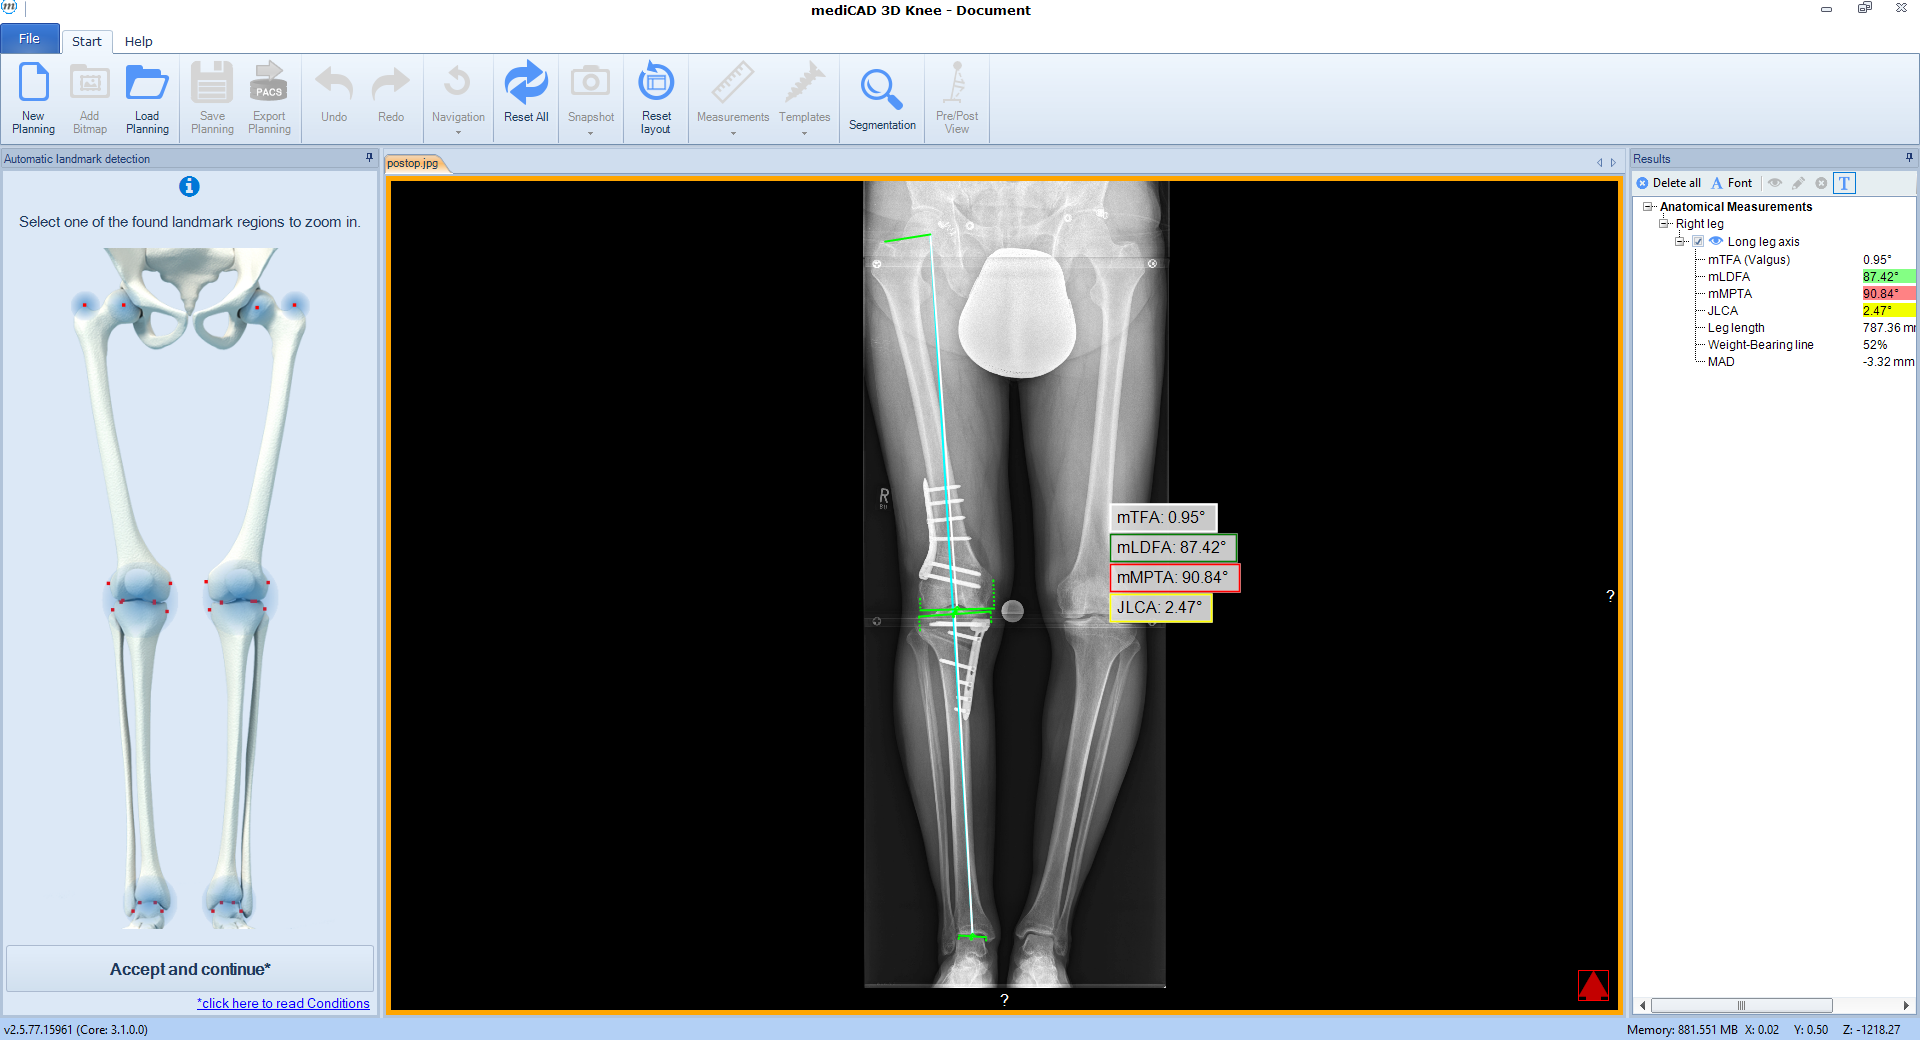

The software automatically detects all necessary landmarks (Fig 1). Based on their position (which can be adjusted manually) the software calculates all essential values (axis, joint lines, and angles) and delivers a detailed report. A traffic light system illustrates normal, intermediate, or pathological values.

Following the deformity analysis, the software automatically recommends a surgical procedure, eg, medial opening wedge high tibia osteotomy, depending on the type of deformity (Fig 2). The user can follow the proposed procedure or choose individual options.

Next, deformity correction is visualized to the preferred new alignment. If a monofocal correction results in pathological joint angles, the implemented algorithm recommends double-level osteotomy and balance the two osteotomies between multiple constraints and normal values such as wedge heights, mechanical medial proximal tibial angle (mMPTA), mechanical lateral distal femoral angle (mLDFA), mechanical tibiofemoral angle (mTFA); (Fig 4).